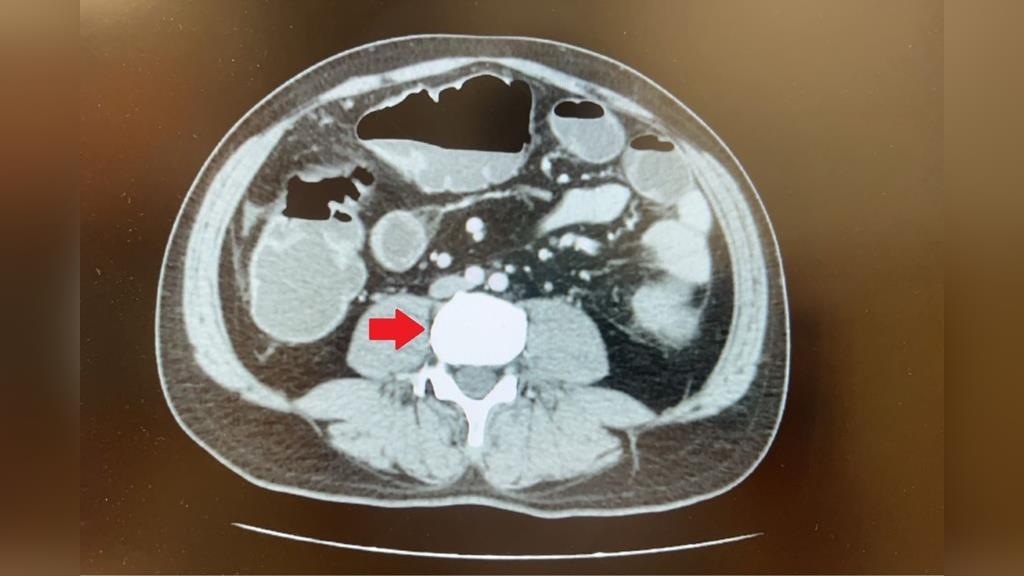

向來健康,沒有家族史的45歲蘇先生,日前長達三天都無排氣、排便,因而腹脹無法進食,至台北慈濟醫院急診就醫;電腦斷層檢查發現他降結腸處有一顆5公分的大腫瘤,導致腸道完全阻塞。醫療團隊高度懷疑大腸癌,但由於腸阻塞無法施行大腸鏡檢查,在與病人討論後,大腸直腸外科醫師陳昱廷為他安排手術切除腫瘤、周圍腸段及淋巴節,術後病理報告確定為已有淋巴轉移的大腸癌第三期,進一步安排後續化學治療。